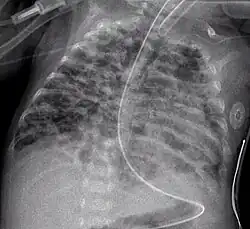

Klinische Symptome können erhöhte Atemfrequenz, vertiefte angestrengte Atmung mit Einziehungen am Brustkorb, vermehrtes Bronchialsekret, Husten, Wachstumsverzögerung und livide Haut- und Schleimhaut sein. Im Röntgenbild der Lunge finden sich u. a. diffus Überblähungsbezirke neben unzureichend belüfteten Bereichen (Atelektasen). Diagnose und Einteilung erfolgen anhand des zu einer ausreichenden Sauerstoffsättigung des Blutes notwendigen Sauerstoffbedarfs zu einem festgelegten Alter des Kindes. Definitionsgemäß ist dabei der Bedarf zum Zeitpunkt eines korrigierten Alters von 36 Schwangerschaftswochen (SSW) maßgebend. Man unterscheidet zwischen einer milden (mit 36 SSW kein erhöhter Sauerstoffbedarf mehr), moderaten (weniger als 30 % Sauerstoff in der Einatemluft notwendig) und schweren Verlaufsform (mehr als 30 % und/oder Beatmung bzw. Atemunterstützung durch CPAP notwendig).[3]